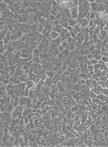

Tumour microenvironment and cancer-associated fibroblasts in particular exhibit tumour promoting abilities that are not present in their normal counterparts (Calvo et al., 2013; Hanahan and Coussens, 2012). Therefore, functional and molecular characterization of the modifications occurring in fibroblasts during tumour progression is essential to fully understand their role in tumour progression. Previous studies have addressed this issue using human fibroblasts and comparing normal and adjacent fibroblasts to tumour-associated fibroblasts (Kalluri and Zeisberg, 2006). However, these studies are hampered by the intrinsic variability of human samples (e.g. pairing, age, genomic landscape, etc). In order to overcome these issues, we used a fully characterised mouse breast cancer model, MMTV-PyMT (Guy et al., 1992; Lin et al., 2003). MMTV-PyMT transgenic mice express the Polyoma Virus middle T antigen under the direction of the mouse mammary tumor virus promoter/enhancer. This is a multifocal luminal breast cancer model that goes through well defined and characterised stages (namely, hyperplasia, adenoma, carcinoma and invasive carcinoma). Interestingly, this model has a 100% incidence, is very desmoplastic (presenting high concentration of fibroblasts) and gives raise to spontaneous metastasis in the lung with 80-94% incidence. Importantly, at least for the inguinal mammary glands (glands 4 and 9), the different tumoral stages are well correlated to the age of the mouse: hyperplasia arising at 6 weeks of age, adenoma between 6-8 weeks of age, carcinoma and invasive carcinoma from 8 weeks onwards. This model allowed us to confidently isolate fibroblasts from different tumoral stages and carefully characterise their functional and molecular properties (Calvo et al., 2013).